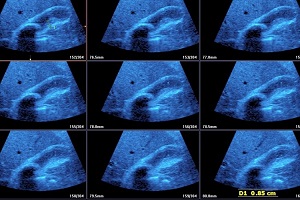

• Solitary Calculi:

• Multiple Calculi

• Findings: Shows presence of calculi in gall bladder/ common bile duct, its mobility & complications.